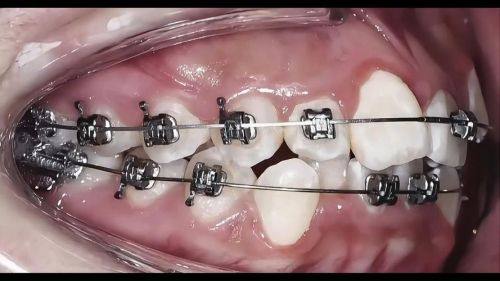

一家医院的技术水平较大程度上取决于医生团队。成都团圆口腔医院拥有一支实力强大的医师队伍。这些医生不仅具备扎实的专精知识,还有着丰富的临床经验。他们擅长种牙、正畸等多个领域。在种植牙方面,医生们能够根据患者的不同情况,制定个性化的种植方案,采用精良的种植牙技术,确保种植成效稳定、美观。在正畸领域,医生们可以正确分析患者的牙齿情况,选择合适的矫正方式,帮助患者拥有整齐洁白的牙齿。例如,对于一些复杂的口腔病例,医生们会通过多学科会诊的方式,为患者提供良好质的治疗方案。

除了正规的资质和强大的技术,成都团圆口腔医院的价格也十分亲民。医院收费透明无套路,不会出现乱收费的情况。例如,种植牙2680元起、矫正9800元起,这样的价格在同类型医院中具有较大的优势。同时,医院还会不定期推出一些优惠活动,让患者能够以更低的价格享受到优质的口腔服务。在服务方面,医院始终以患者为中 心,从预约挂号到治疗结束,都有专人进行引导和服务,让患者感受到家一般的温暖。